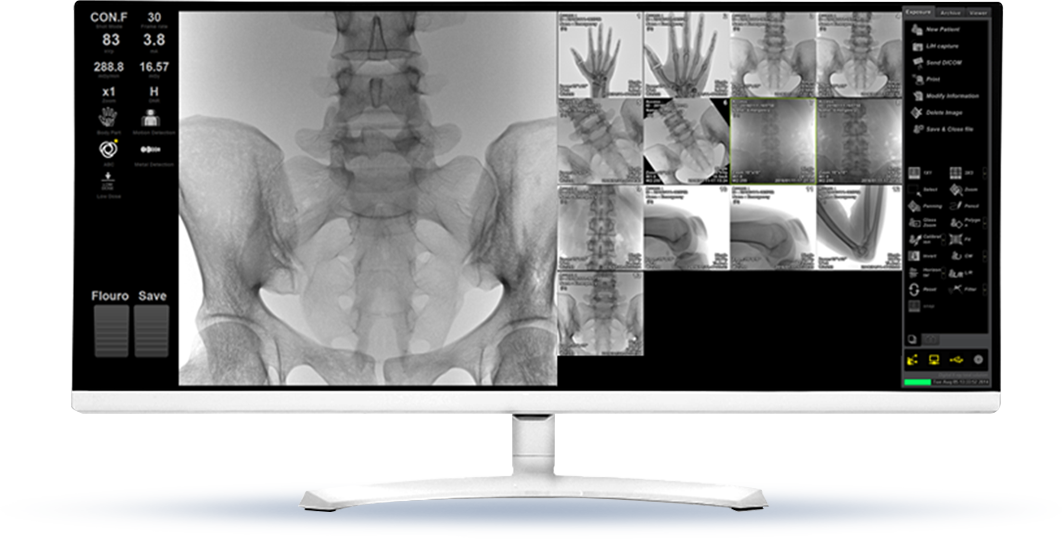

ZENIS™ software provides a total solution from operation, image storage, and management.

26cm*26cm Flat Panel Detector provides excellent image quality (Max. 6.8MP) with large FOV(*). * Field Of View